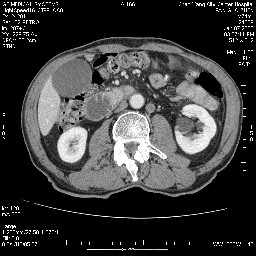

双肾多发小囊肿;左肾积水。

十二指肠降段扩张,水平段狭窄成鼠尾状,肠壁明显增厚,胰腺勾突增大成不均匀强化,其内可见低密度区,胆囊增大,1十二指肠水平段腺癌侵犯胰腺勾突可能大,2胰腺癌侵犯十二指肠(只有胆囊增大没有肝内外胆管扩张不好解释)代除外.

12指肠壁可见结节状隆起,考虑为12指肠腺癌并梗阻可能性大!

十二指肠降段扩张,水平段狭窄成鼠尾状,肠壁明显增厚,胰腺勾突增大成不均匀强化,其内可见低密度区,胆囊增大,1十二指肠水平段腺癌侵犯胰腺勾突可能大,2胰腺癌侵犯十二指肠 。

今日手术结果:胰腺钩突癌侵犯十二直肠,腹腔淋巴结转移.

十二指肠降段扩张,水平段狭窄成鼠尾状,肠壁明显增厚,胰腺勾突增大成不均匀强化,,胆囊增大,十二指肠水平段腺癌侵犯胰腺